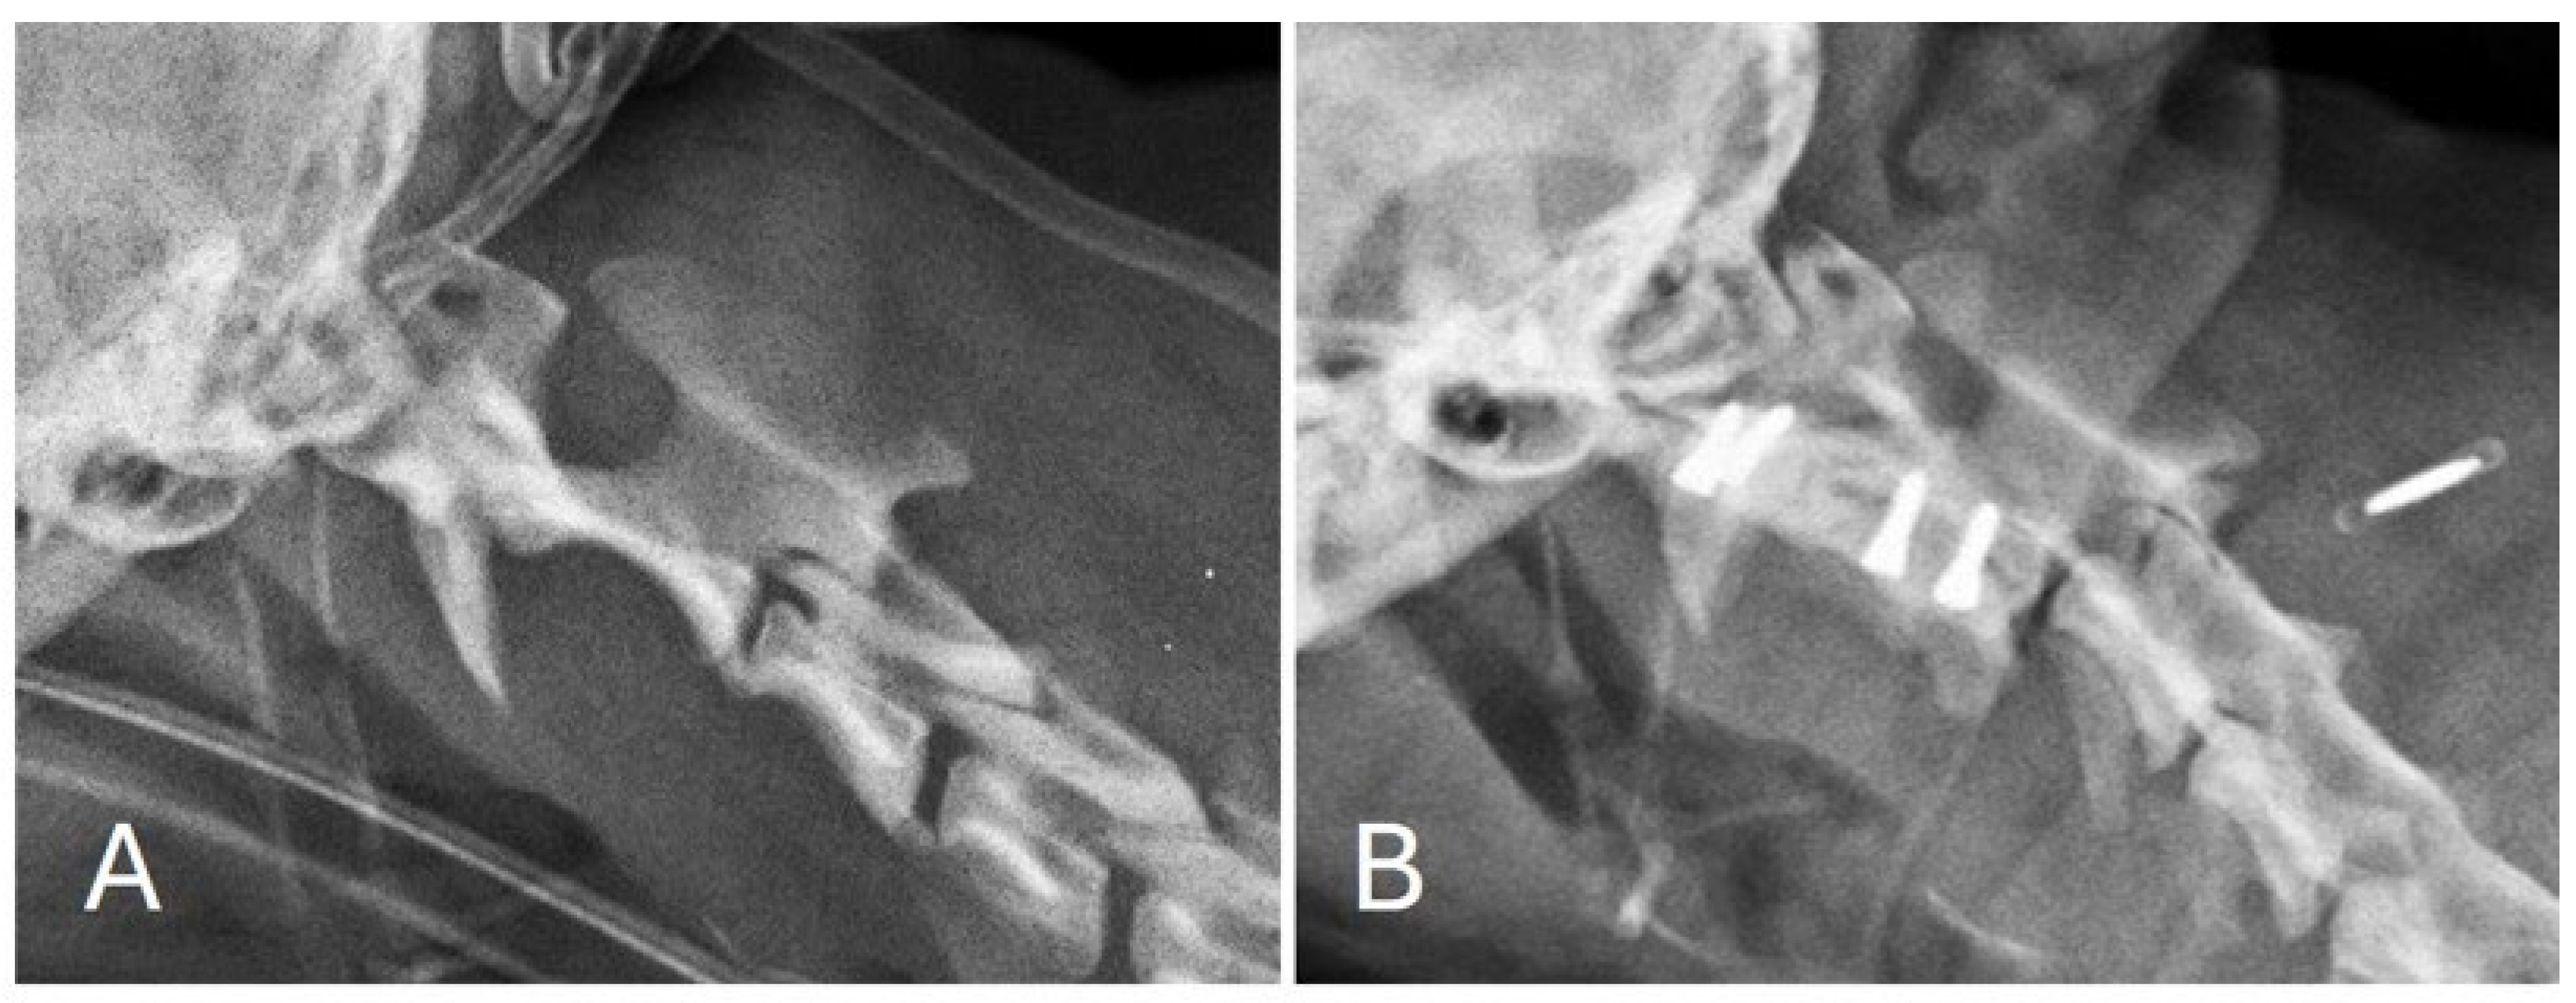

Post-operative images showed correct implant positioning and normal location of the dens within the respective fovea along the ventral arch of C1 (Figure 3 and Figure 4).

Figure 3. Lateral view of the cervical spine before (A) and after (B) surgical treatment. Correct screw insertion can also be observed.